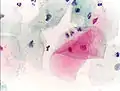

Micrograph of a Pap test showing trichomoniasis. Trichomonas organism seen in the upper right. Pap stain.